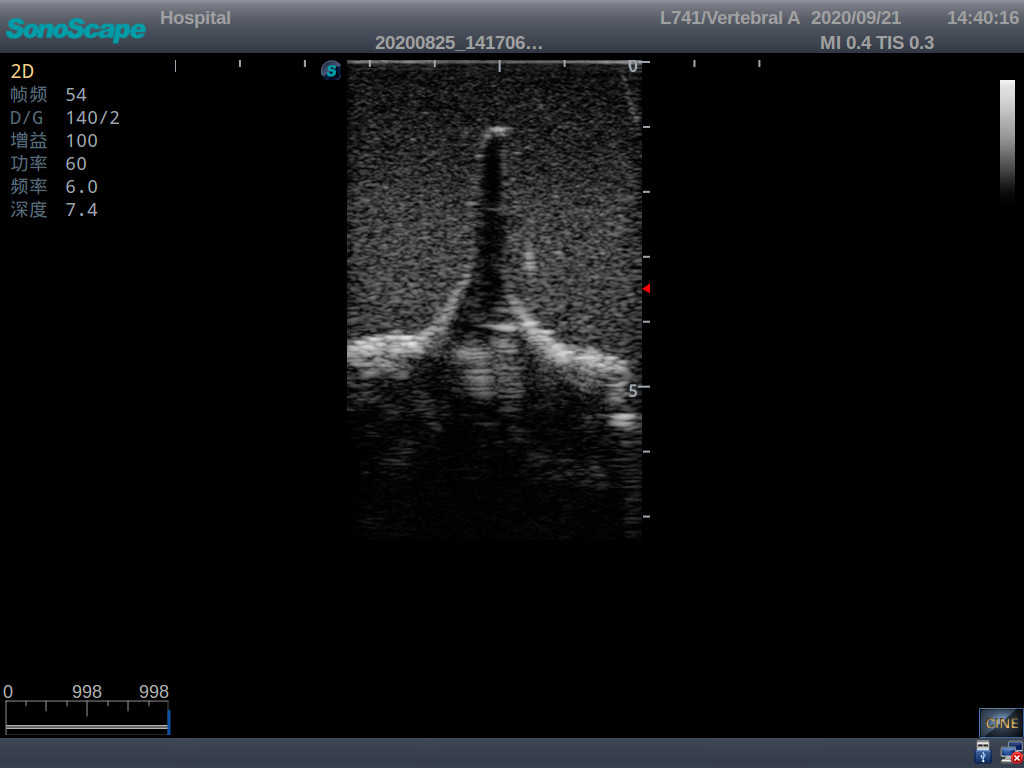

This model is an ideal choice for ultrasound-guided adult lumbar puncture training with true-to-life skin feel and touch, accurate anatomical structures as well as real clinical ultrasound images. Realistic resistance to needle tips and correct landmarks provide excellent hands-on experience.

2)  Real clinical ultrasound images

3)  Compatible with various real ultrasound machines

1)   Ultrasound-guided lumbar puncture practice